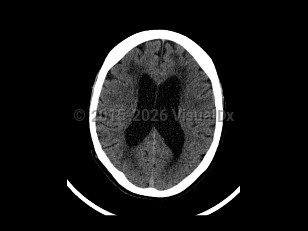

Normal pressure hydrocephalus (NPH) is a common neurologic disorder resulting in slowly progressive gait abnormalities, cognitive deterioration, and urinary incontinence.

Gait and balance dysfunction typically develop early in the course of NPH, whereas cognitive symptoms and incontinence usually appear as the disease progresses. The typical gait abnormality in NPH is a broad-based, slow, short-stepped, "stuck to the floor" or "magnetic" movement. Postural stability is usually impaired, and a history of falls may be reported. The cognitive deficits are typically impairments in attention, psychomotor speed, and executive dysfunction. Patients with more advanced NPH can develop generalized cognitive dysfunction. Disturbances of bladder function in NPH result from detrusor hyperactivity secondary to a loss of central inhibitory control. Increased urinary frequency and urgency and subsequent incontinence can develop.

Approximately 40%-75% of patients with suspected NPH are subsequently found to have other comorbid neurodegenerative diseases such as Alzheimer disease. NPH patients with other comorbid neurodegenerative conditions are thought to have a poorer response to CSF shunting.